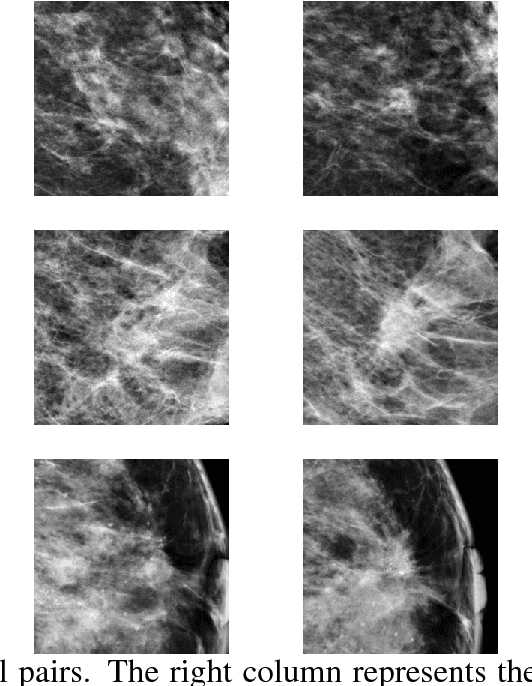

Abstract:Purpose: Risk-stratified breast cancer screening might improve early detection and efficiency without comprising quality. However, modern mammography-based risk models do not ensure adaptation across vendor-domains and rely on cancer precursors, associated with short-term risk, which might limit long-term risk assessment. We report a cross-vendor mammographic texture model for long-term risk. Approach: The texture model was robustly trained using two systematically designed case-control datasets. Textural features, indicative of future breast cancer, were learned by excluding samples with diagnosed/potential malignancies from training. An augmentation-based domain adaption technique, based on flavorization of mammographic views, ensured generalization across vendor-domains. The model was validated in 66,607 consecutively screened Danish women with flavorized Siemens views and 25,706 Dutch women with Hologic-processed views. Performances were evaluated for interval cancers (IC) within two years from screening and long-term cancers (LTC) from two years after screening. The texture model was combined with established risk factors to flag 10% of women with the highest risk. Results: In Danish women, the texture model achieved an area under the receiver operating characteristic (AUC) of 0.71 and 0.65 for ICs and LTCs, respectively. In Dutch women with Hologic-processed views, the AUCs were not different from AUCs in Danish women with flavorized views. The AUC for texture combined with established risk factors increased to 0.68 for LTCs. The 10% of women flagged as high-risk accounted for 25.5% of ICs and 24.8% of LTCs. Conclusions: The texture model robustly estimated long-term breast cancer risk while adapting to an unseen processed vendor-domain and identified a clinically relevant high-risk subgroup.